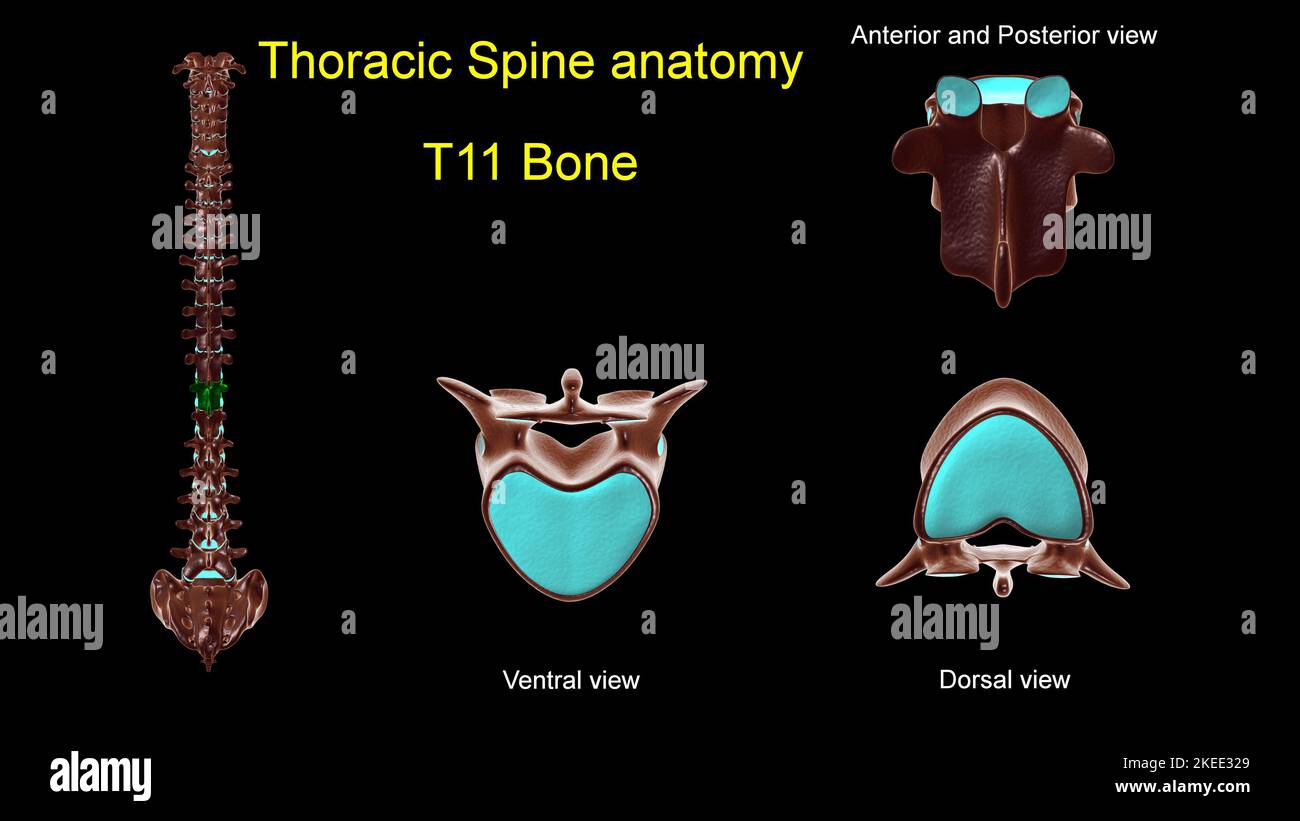

RF2KEE329–Colonna toracica T 11 anatomia ossea per concetto medico 3D Illustrazione con vista anteriore e posteriore